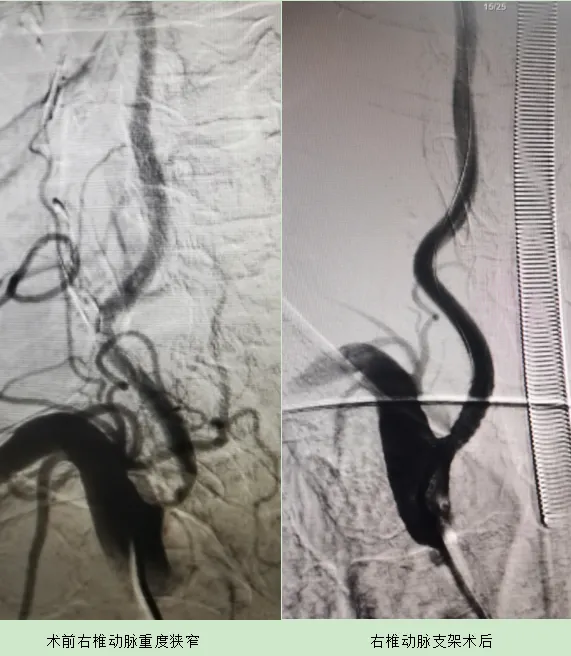

李闊主任再次和患者家屬交代,王老血管多處重度狹窄,隨時有閉塞的風(fēng)險,建議抓緊時間進手術(shù)室,行全腦血管造影。腦血管病二科、放射介入科、麻醉科快速聯(lián)動,立刻安排急診上臺。術(shù)中基底動脈重度狹窄、右側(cè)椎動脈開口重度狹窄、左側(cè)椎動脈閉塞、右側(cè)頸內(nèi)動脈重度狹窄,符合手術(shù)指征,經(jīng)過短暫的協(xié)商,爭取一次為患者解決多處頑疾。

安排介入手術(shù),造影準(zhǔn)備基底動脈支架。“主任、基底動脈閉塞了!”,這嚇壞了手術(shù)的醫(yī)生,怎么回事啊?手術(shù)室所有的人立刻揪住了心。“患者基底動脈剛才就幾近閉塞,這是供血不足閉塞了???、抓緊開通”。在劉鐵艷主任的指揮下,張傳鎖醫(yī)生加快了手上的動作?!盎讋用}開通了!”,手術(shù)室所有人都長舒了一口氣,手術(shù)非常順利:右側(cè)椎動脈開口、基底動脈、右側(cè)頸內(nèi)動脈全部順利開通。術(shù)后經(jīng)過治療王老再次恢復(fù)了往日的精神面貌。